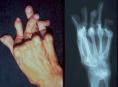

ArtrosisMás del 70% de los mayores de 50 años tienen signos radiológicos de artrosis, siendo las localizaciones más frecuentes la cervical, la lumbar y las interfalángicas distales de las manos, según destacan especialistas asistentes al XXXII Congreso de la Sociedad Española de Reumatología (SER), que se celebra en Valencia.

La artrosis es la enfermedad articular más frecuente en España, afectando a 7 millones de españoles, aunque como destacó el Dr. Pere Benito Ruiz, jefe del Servicio de Reumatología del Hospital del Mar de Barcelona, las articulaciones "no siempre se degeneran con la edad".

Aunque hoy día se desconoce el mecanismo exacto por el que se inicia toda la cadena de acontecimientos que conducen a la artrosis, se sabe que hay unos factores de riesgo que favorecen su aparición y empeoran el pronóstico, como son todos los problemas que afectan al cartílago articular, los microtraumatismos repetidos y la sobrecarga que se produce en determinadas actividades laborales o deportivas, o como consecuencia de la obesidad.

Según informaron los expertos que han acudido a este Congreso, la

artrosis suele aparecer en la década de los 50 de cada paciente, y

aumenta rápidamente con la edad, siendo más frecuente en las mujeres y afectando sobre todo a las manos, rodillas, caderas y columna. Aunque es una enfermedad con baja mortalidad, su alta prevalencia y perdurabilidad, hacen que "su carga social sea enorme".